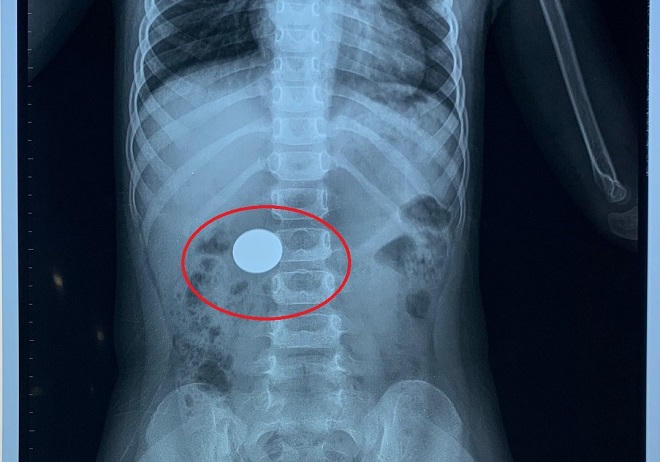

Qua chụp X-quang, các bác sĩ xác định có một dị vật hình tròn, nhìn giống đồng xu trong dạ dày của bệnh nhân. Các bác sĩ Nhi và Nội soi tiêu hóa đã tiến hành hội chẩn, tiến đến chỉ định nội soi can thiệp thực quản dạ dày để gắp dị vật, tránh những biến chứng không mong muốn có thể xảy ra.